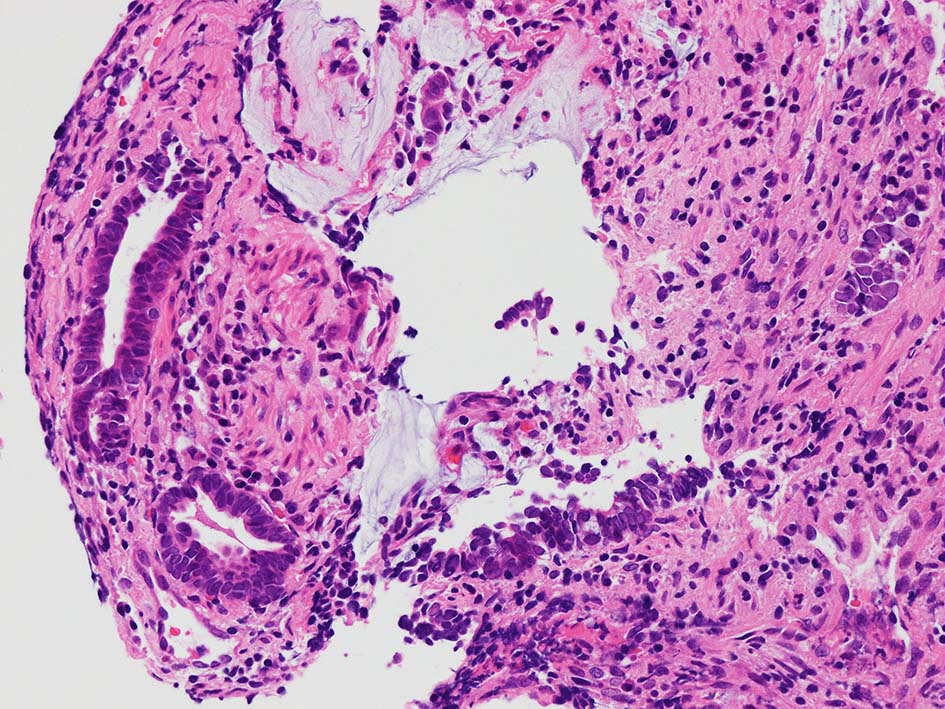

desmoplastic fibrosis, 粘液浸潤のみられる組織片にはsig, porのadenocarcinoma浸潤が確認される.

GI tract, とくに大腸癌の膀胱浸潤/転移を最初に考えた.